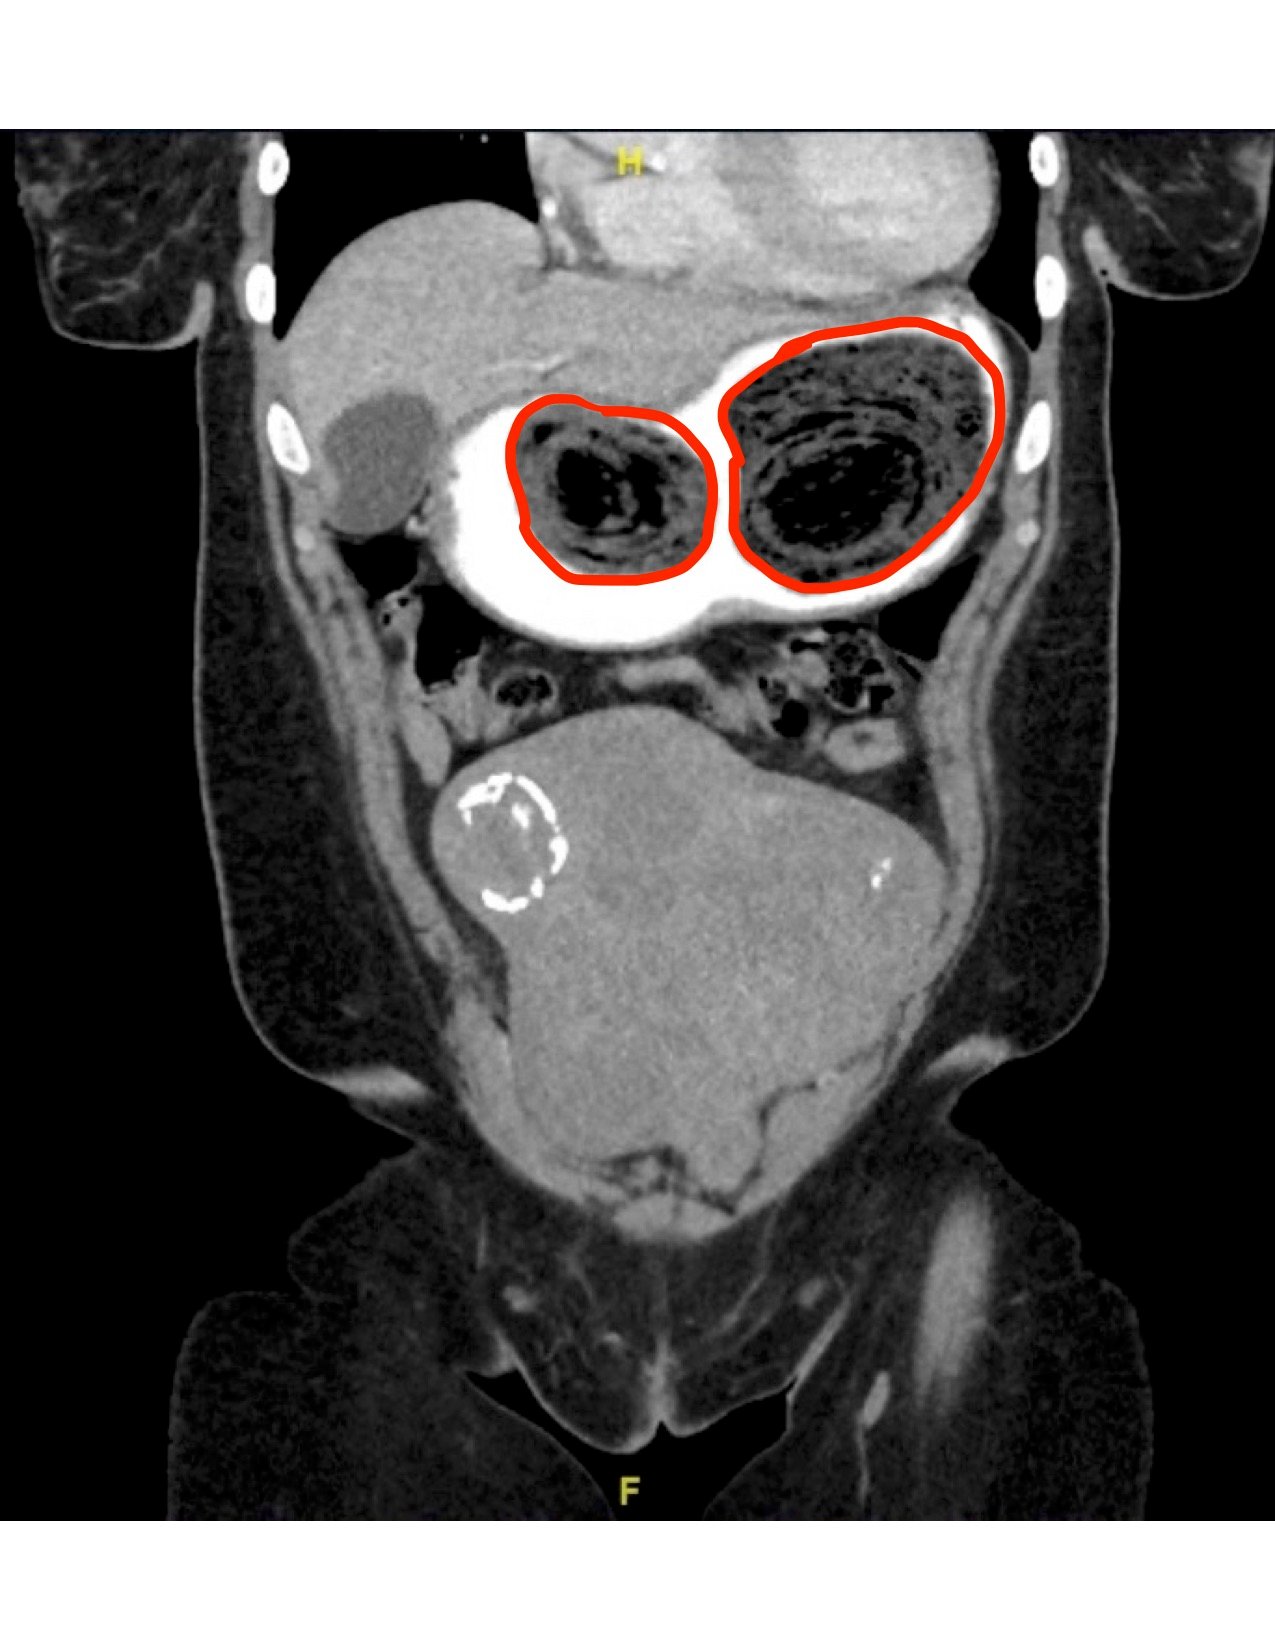

Computed tomography (CT) of the abdomen and pelvis with oral and intravenous contrast was ordered to evaluate her symptoms. The CT showed three large collections of ingested material seen as hypodense material with circular rings surrounded by the hyperdense oral contrast (see red outlines). These findings are consistent with bezoars, the largest of which measured 11.5 x 7.8 cm. There was also thickening of the gastric wall (see blue outline), most notably at the pylorus, consistent with partial obstruction.